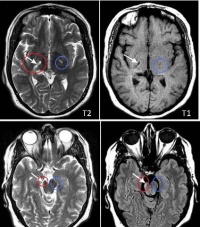

上运动神经元性瘫痪(upper motor nearon paralysis ),亦称中枢性瘫痪,是由皮层运动投射区和上运动

神经元径路(皮层脊骨髓束和皮层脑干束)损害而引起。因瘫痪肌的肌张力增高,故又称痉挛性瘫痪或硬瘫。因为纤维束的纤维和细胞排列得相当紧密,故上运动神经元瘫痪多为广泛性的,波及整个肢体或身体的一侧。凡皮层运动投射区和上运动神经元径路受到病变的损害,均可引起上运动神经元性瘫痪,常见的病因有颅脑外伤、肿瘤、炎症、脑血管病、变性、中毒、以及内科某些疾病,如糖尿病、血卟啉病、大红细胞性贫血及维生素B12缺乏等。同于病变损害的部位不同,在临床上可产生不同类型的瘫痪,如单瘫、偏瘫、截瘫、四肢瘫等,尽管瘫痪的表现不同,但它们都具有相同的特点,即瘫痪肌肉张力增高、腱反射亢进、浅反射消失、出现所谓连带(联合)运动和病理反射,瘫痪肌肉不萎缩,电测验无变性反应。

同一侧上肢及下肢肌肉瘫痪称为偏瘫。有时伴有同侧下面部肌肉及舌肌的瘫痪。自大脑皮质运动区开始经内囊、脑干至脊髓前角细胞之间的神经径路的任何部位病变,均可产生偏瘫,起病隐袭,呈缓慢进行性发展的偏瘫,病因多为颅内占位性病变,如脑肿瘤、脑脓肿、颅内血肿、脑寄生虫等,如表现为脊髓特点的进行偏瘫其病因多为脊髓肿瘤、脊柱结核、脊柱增生性病变、肥厚性硬脊膜炎等。突然起病,急速发展的偏瘫多由脑血管病引起。主要为一侧上下肢的运动障碍。在临床上有四种表现形式:①意识障碍性偏瘫:表现为突然发生意识障碍,并伴有偏瘫,常有头及眼各一侧偏斜。②弛缓性偏瘫:表现为一侧上下肢随意运动障碍伴有明显的肌张力低下,随意肌麻痹明显面不随意肌则可不出现麻痹,如胃肠运动、膀胱肌等均不发生障碍。③痉挛性偏瘫:一般的是由弛缓性偏瘫移行而来,其特点是明显的肌张力增高。上肢的伸肌群及下肢的屈肌群瘫痪明显,肌张力显著增高,故上肢表现为屈曲,下肢伸直,手指呈屈曲状态,被动伸直手有僵硬抵抗感。④轻偏瘫:在偏瘫极轻微的情况下,如进行性偏瘫的早期,或一过性发作性偏瘫的发作间隙期,瘫痪轻微,如不仔细检查易于遗漏。